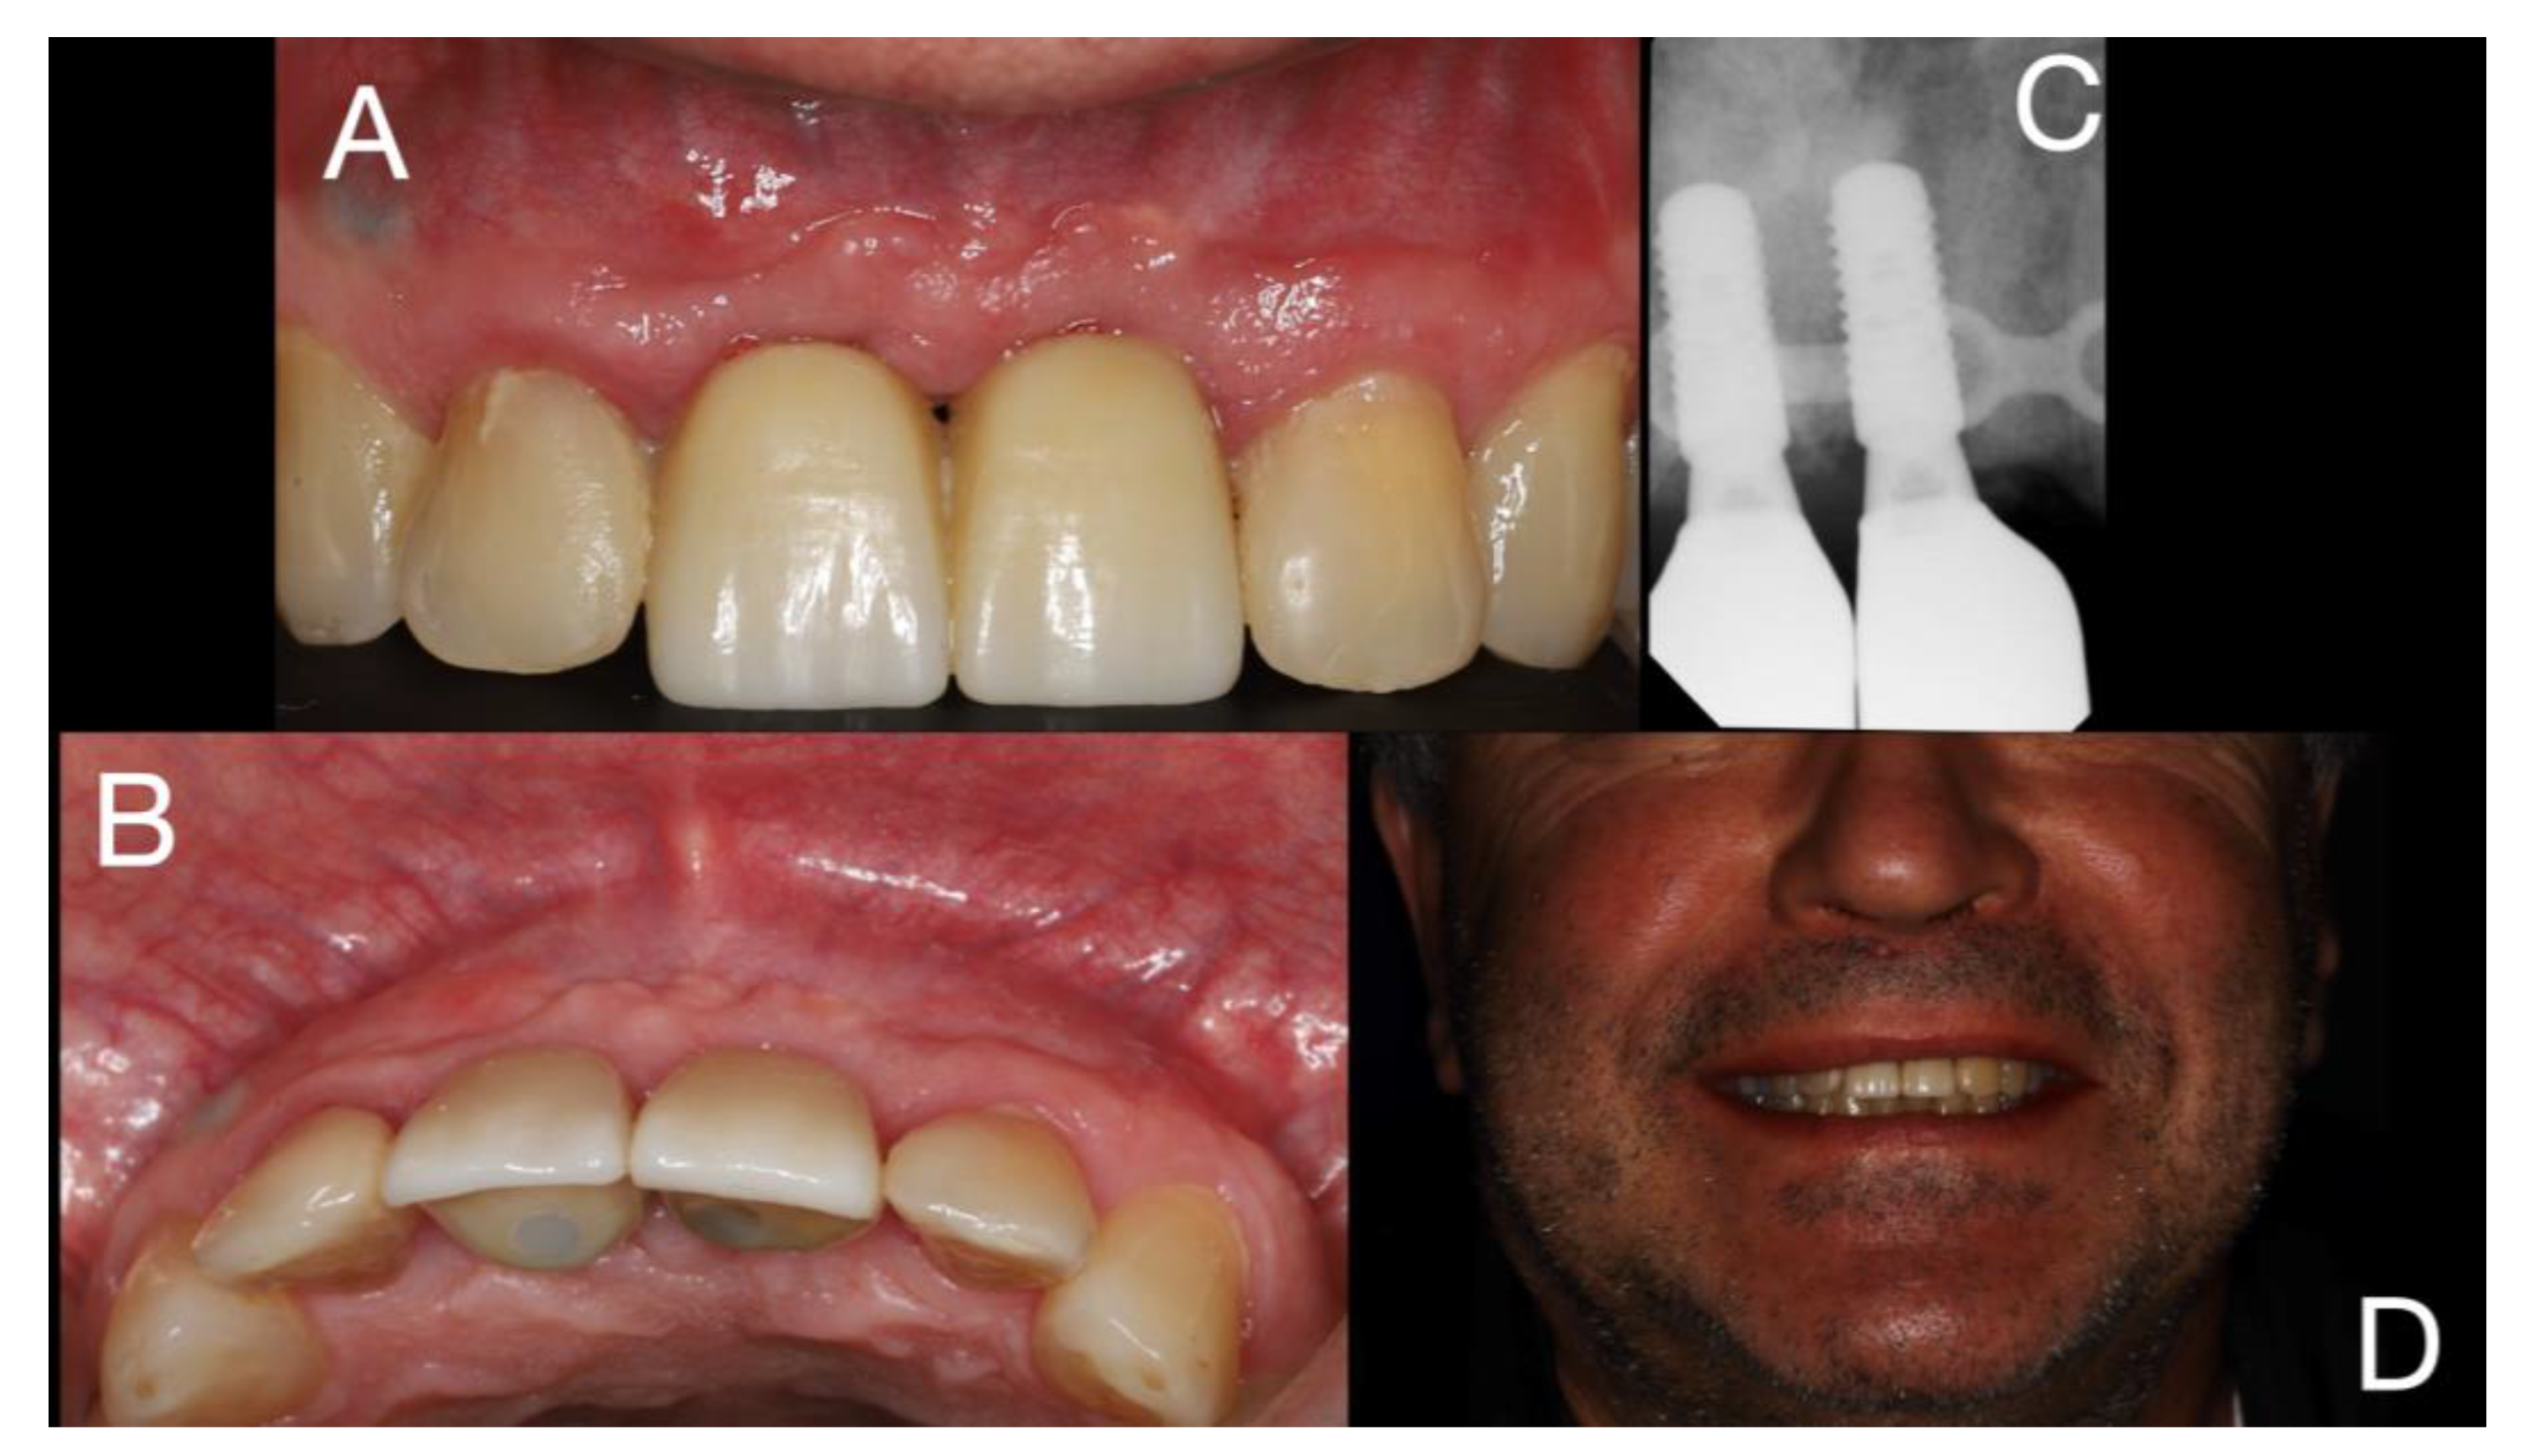

Figure 3. 6 weeks after tooth extraction with healead of soft tissue – A -frontal view; B - occlusal view.

After 6 weeks for healing of soft tissue (Figure 3), the surgery of cyst enucleation and guide bone regeneration with fence technique [9] was performed.

A new endodontic treatment was performed at tooth 12 and the tooth 11 was extracted; a partial removal prothesis was placed.